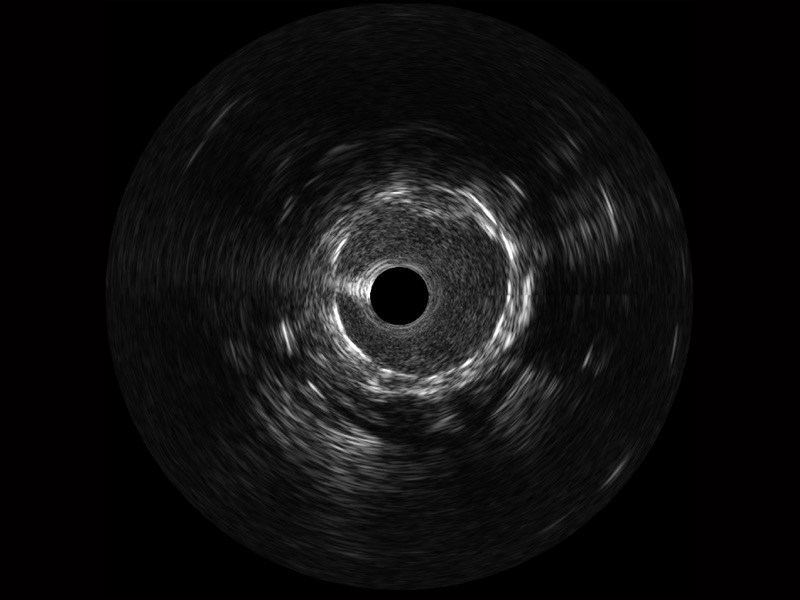

狗万官方网站超宽频成像技术覆盖20-80MHz1或20-90MHz2频率范围, 提供优异的分辨力同时也保证充足的穿透深度

对比传统IVUS导管成像,狗万官方网站宽频IVUS图像的近场支架梁显影更细腻,远场中膜外血管仍清晰可辨,兼顾远中近,兼顾分辨力与穿透深度